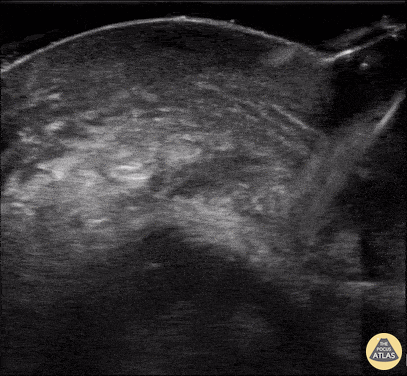

Orbital - Ruptured Globe

This patient sustained blunt trauma to the eye from a fireworks injury. CT scan performed prior to POCUS showed intra-orbital hematoma and complete absence of any globe tissue. The patient was taken to the OR for primary enucleation, washout, and closure. Earl “Quinn” Cummings, MD @resus_bae Assistant Professor; MUSC Emergency Medicine/Ultrasound; MUSC Pediatric Emergency Medicine